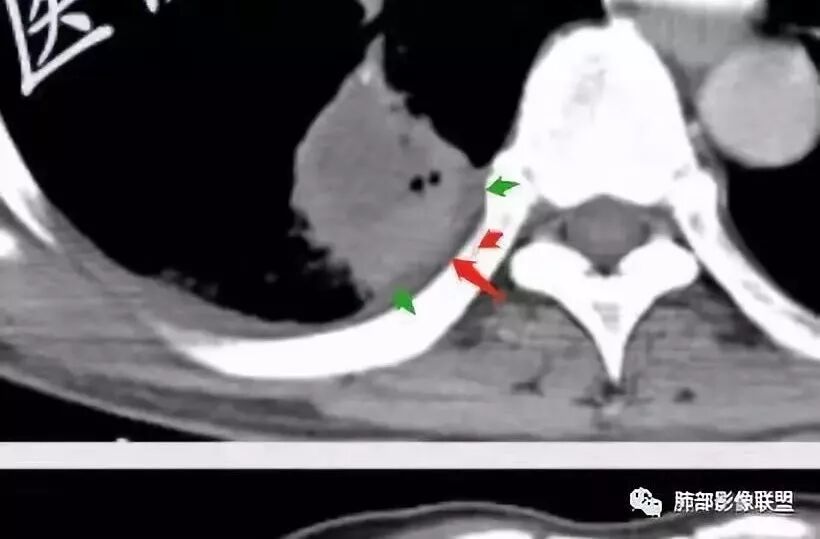

少量积液反衬外壁更好看,靠近胸膜侧有很多积液不连续,断掉,局部膨隆在外面。很大一部分是连续的,但有些部分是不连续的。有膨隆我就很难判断,病灶的膨隆是张力引起的,还是远端栽赃引起的?局部的胸膜有变化的。所以我怀疑有栽赃的趋势,为什么说趋势,是因为没看到外面一个侵犯的迹象,但是层厚原因我有些地方我不敢说,有没有侵犯。

南边:

你看我标的这个地方,我就觉得这个病灶有侵犯性,附近旁边都有一个低密度线影,局部就没了,病灶似乎直接到个肋骨的胸膜脂肪间隙下,这些地方都有类似迹象,把它当成一个大的肿块,有分叶,近端有坏死、空洞,壁外围还有有些毛糙,腔内也有些索条影。颅脑内像个转移瘤的特点,转移瘤,淋巴瘤,脓肿?脓肿腔内脓液粘稠,弥散受限,这个腔内DWI不高,这个让我犹豫.按理脓肿也要考虑.